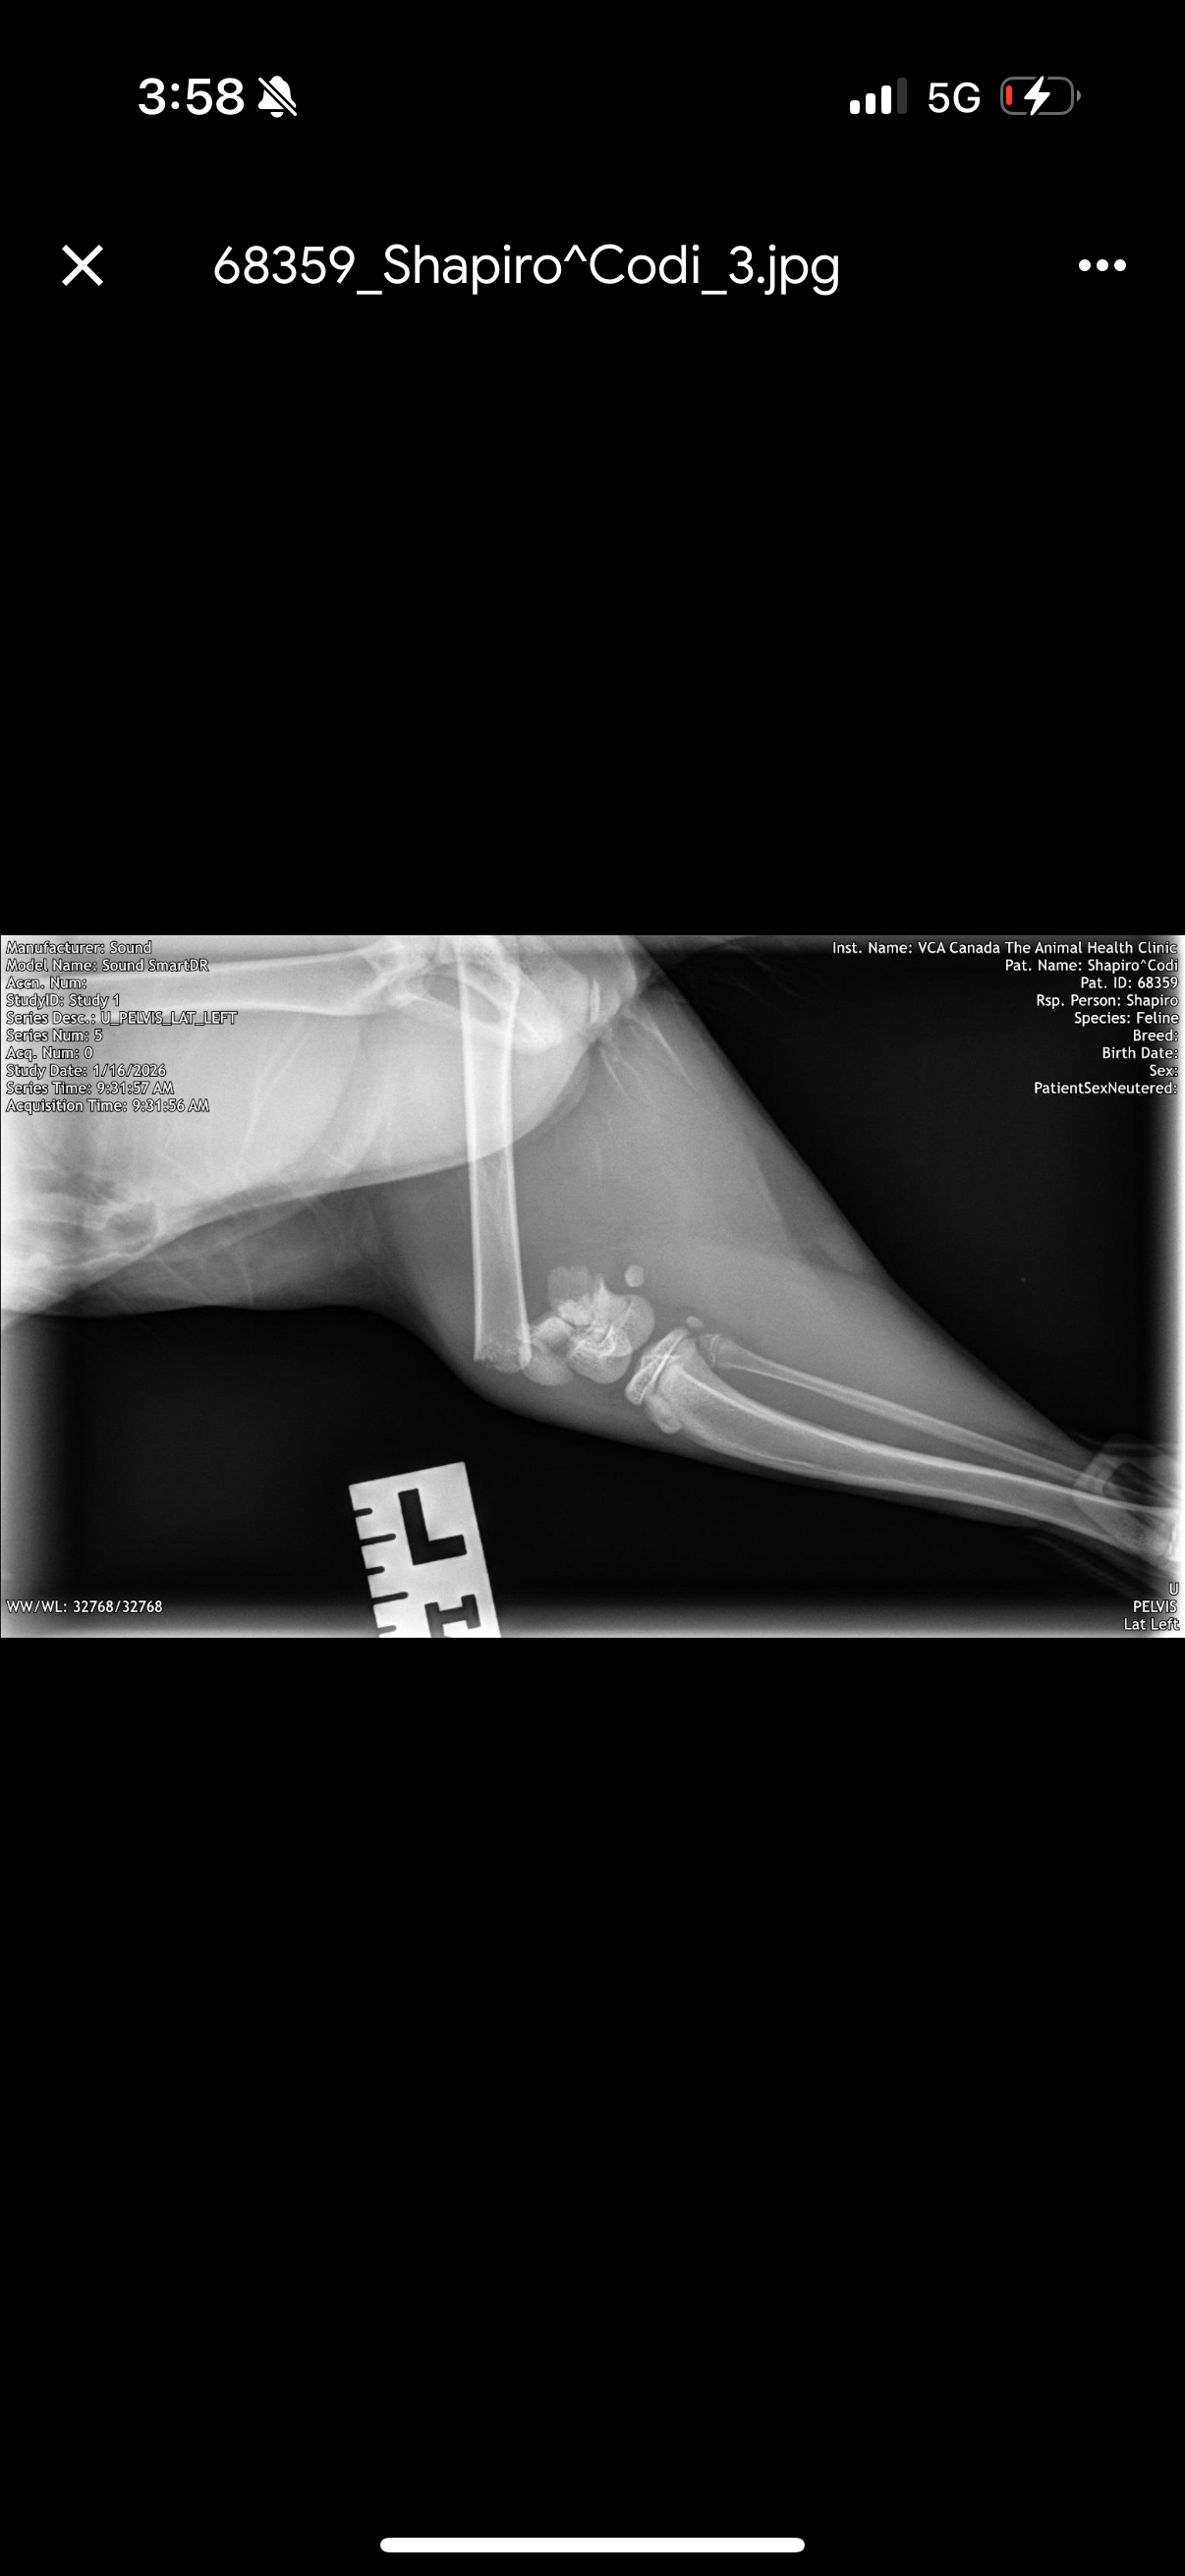

This is Codi, my 4.5–5-month-old kitten. She’s sweet, playful, and still just a baby. A sudden accident left her with a severe fracture to her left back leg, and she’s in pain but can absolutely recover with treatment.

Because I don’t have pet insurance, the emergency vet quoted up to $7,500 + tax for orthopedic surgery — a cost I simply cannot afford. I live in Montreal and am actively pursuing lower-cost options, and discussing hind-leg amputation as a last resort, which is a humane and successful option for many cats. Even these options still cost thousands of dollars, and time is critical.